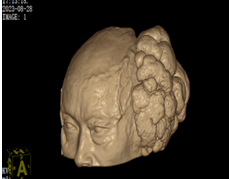

20多年前,老牟头顶长了一个巨大的肿物,由于父母双亡、无兄弟姊妹、无儿无女,独身且贫困的他选择了任由肿物生长,村里人都把他看作“怪人”,远远地躲着他。前些时日,政府给他办理了“五保户”,有了医保和政府兜底,在村里人的催促下,老牟来到合江县人民医院神经外科寻求治疗。 经测量,该头皮肿物直径达17cm,肿瘤呈现菜花状,表面有明显破溃及分泌物,表面血管怒张,远看像拥有两个并列的头颅的“怪人”。所幸的是,患者头颅CT显示肿瘤位于颅外,与脑组织并无关联。